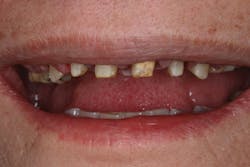

In the second case, a full arch of full-contour, anterior zirconia restorations are primed with zirconia primer and ready to be tried in (figure 6). Due to the patient's short clinical crowns, TheraCem was chosen to provide maximum retention of the zirconia restorations. In this case, attrition due to bruxism had reduced the height of the patient's teeth, and almost no vertical reduction was performed from first premolar to first premolar (figure 7). After try-in, the prostheses were rinsed and dried, and the front four crowns were delivered with TheraCem (figure 8). After preliminary cleanup of the cement, the upper left teeth were rinsed and gently dried (figure 9). The upper left restorations were then delivered with TheraCem (figure 10). This was followed up with another preliminary cleanup of the cement (figure 11). A retracted view shows the final restorations after a thorough cleanup (figure 12).

Figure 7: Patient's teeth before restoration